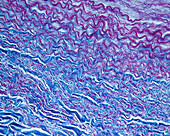

13613450 - Elastic lamellae in aorta, light micrograph

13613436 - Elastic lamellae in aorta, light micrograph

13613447 - Elastic lamellae in aorta, light micrograph

13613449 - Elastic lamellae in aorta, light micrograph

13613433 - Elastic lamellae in human aorta, light micrograph

12360842 - Elastic lamellae, light micrograph